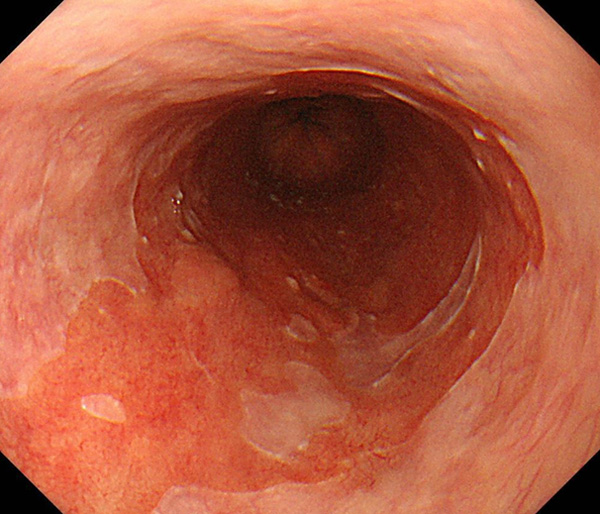

内視鏡所見と病理組織像の1対1対応が可能な症例を公募いたします。主にLSBEに発生した早期癌(HGDを含む)を対象としますが、興味深い症例であればSSBE癌でも結構です。採否は世話人へご一任ください。

症例呈示希望者は応募用紙に記入の上、代表的な内視鏡(2枚)、切除標本(新鮮、固定)、切り出し図、マッピング、代表的組織像とともに、Barrett 食道研究会事務局 barrett.shinshu@gmail.comへお申し込み下さい(10MB以下でお願い致します)。

特に、本邦では極めて稀なlong segment Barrett’s esophagus(LSBE)から発生した早期癌は、診断に難渋する場合も多く、欧米ではランダム生検による検出が標準的とされています。背景のBarrett食道もろとも全体を内視鏡切除+ラジオ波焼灼する欧米と異なり、ESDで内視鏡的な局所切除が基本の本邦では、存在診断+範囲診断(特に水平)を的確に行うことが不可欠です。

そのためには、一流の病理医による組織学的診断とエキスパート内視鏡医による拡大内視鏡像との一対一対応を徹底的に行うことで、『本来、見えないであろう拡大所見の先にある組織構築像が診えてくる』所まで内視鏡診断レベルを上げていく必要があります。その実現には、一対一対応を追究した症例(特にLSBE発生例)1例でも多く経験するしかありません。本研究会でBarrett食道腺癌(LSBE発生早期病変)を共に学び、拡大内視鏡像の一歩先を診るスキルを習得しましょう!一人でも多くの皆様のご参加をお待ちしています。

2026年1月24日開催の第19回研究会でご提示した検討症例です。 (画像をクリックすると拡大します)